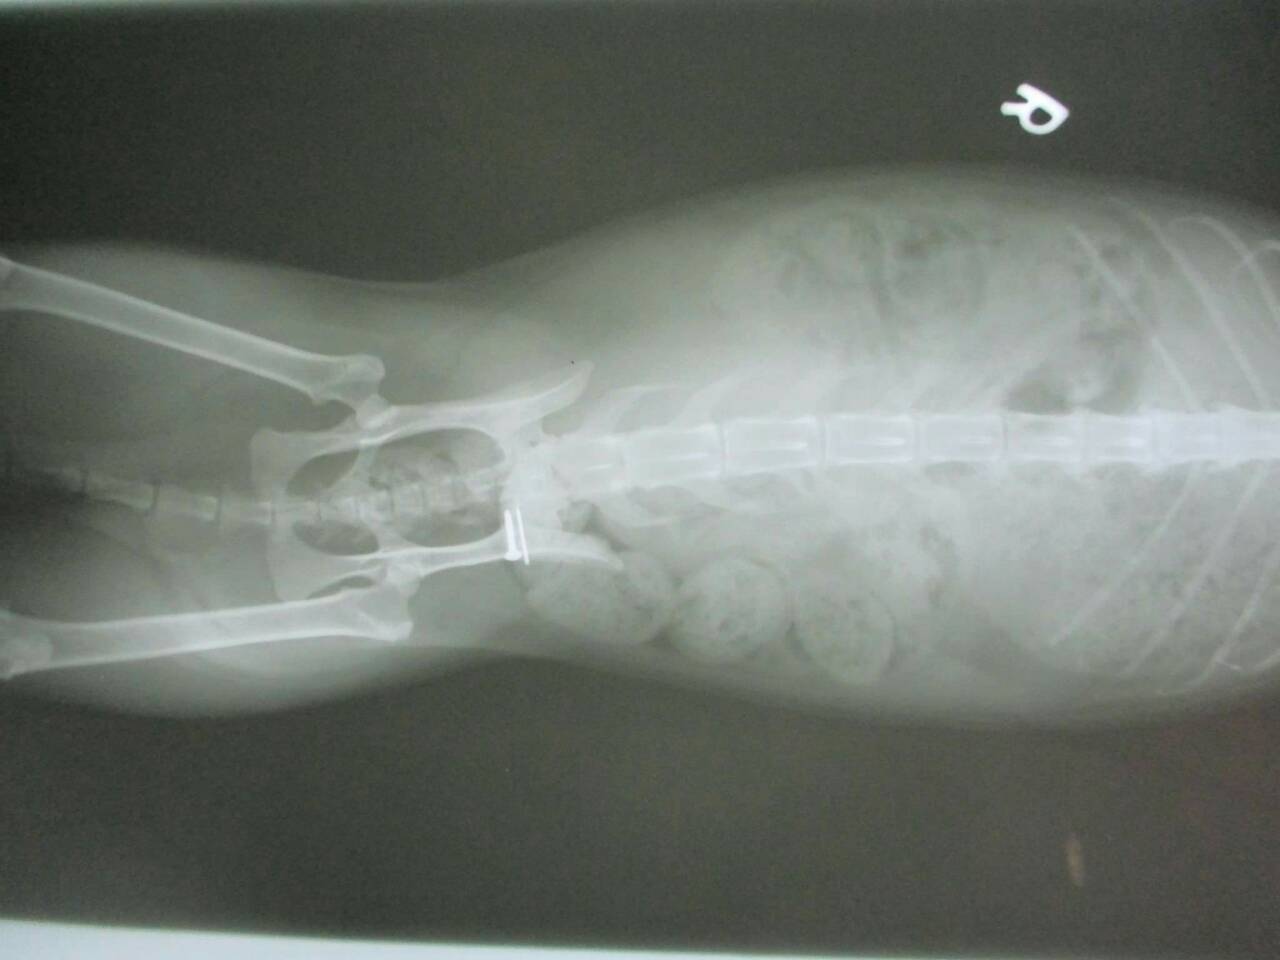

主題: 壽山收容所 背傷癱瘓貓 申請者姓名: 劉素鳳 花色: 申請日期: 2016-02-02 23:46:43 申請者部落格: 申請者臉書網址: https://m.facebook.com/sufeng.liu?ref=bookmarks 所在縣市/合作醫院: 高雄市/樂生動物醫院 治療費用: 3200元 需求人數: 8人 已結案 (2024-06-01 13:41:09) 報名人員: Freesia Tsai(已付款)、Amber Chung x2(已付款)、兔子(已付款)、karena(已付款)、Nancy Wu(已付款)、Tina Chen(已付款)、吳金英(已付款)、 候補人員: 動物病情說明: 壽山收容所專案的貓咪,這隻三花貓小刀 原本背部傷口有在癒合了,但在前一家醫院觀察後發現他後軀的神經反射有問題,後腳目前是都無法站,而且有點癱瘓的狀況,只能靠前肢撐著。

醫生初步檢查左邊腸薦關節有做手術,胸腰椎交接處(T13~L1)有受傷,可能是造成後驅癱瘓的主因,左右兩側後腳還有反射但左邊反應較差,傷口部分目前還好並無分泌物但後面幾天還是需觀察,如有分泌物出現則有可能又需做清創手術,血檢並未有異常,貓咪目前食慾還不錯,所以並未上點滴,目前會先就傷口照護為主, 醫生建議貓咪轉到大醫院做針灸的治療,努力應該會有康復的機會, 謝謝大家幫助這貓咪^^ . 、